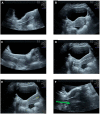

Figure 8.

Ultrasound images showing various factors related to a transabdominal ultrasound-guided embryo transfer. (A) Zoom window focused on the uterine cavity. (B) Deep field view of embryo transfer (ET) during catheterization. (C) Retroverted uterus ET. (D) ET catheter approaching the fundal part of the endometrium. (E) Measurement of distances between tip of catheter and fundal endometrium and between embryo bubble and endometrium. (F) Artefacts during ET: example of mirror image artefact (uterus is anteverted but there is a false image showing a retroverted uterus).